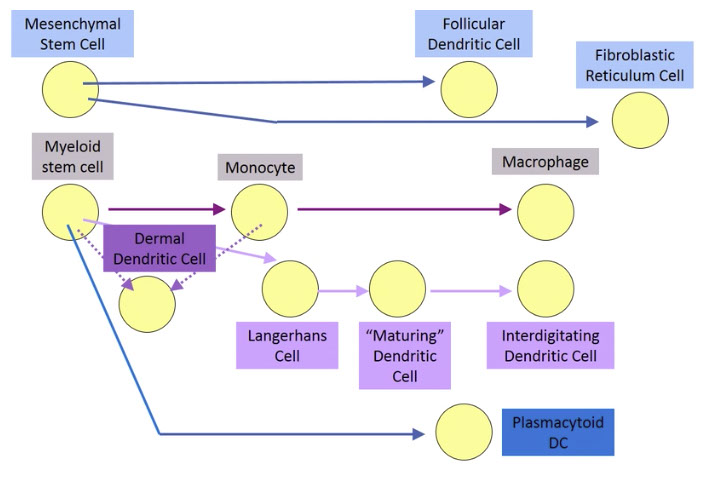

Histiocytic and dendritic cell neoplasms

Hemophagocytic Lymphohistiocytosis, Rosai-Dorfman disease (see Spleen and Lymph Node)

Histiocytic sarcoma

Tumors derived from Langerhans cells

- Langerhans cell histiocytosis (LCH)

- Langerhans cell sarcoma (LCS)

Indeterminate dendritic cell tumor

Interdigitating dendritic cell sarcoma

Follicular dendritic cell sarcoma

- Inflammatory pseudotumour-like follicular/fibroblastic dendritic cell sarcoma

Fibroblastic reticular cell tumor

Disseminated juvenile xanthogranuloma

Erdheim-Chester disease